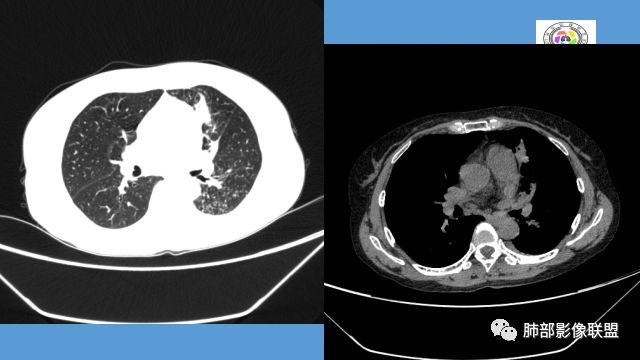

左上胸缩小,但是左上叶部分实变,边缘膨隆,内部有含气支气管,粘液栓,近端支气管堵塞

前端支气管通畅,部分稍扩张,走形自然

实变区支气管内粘液栓明显

上叶支气管堵塞处稍萎缩、凹陷,附近壁增厚,内可见小点状钙化

分析:支气管粘液栓、支气管堵塞处萎缩、钙化,支气管通畅处部分扩张,树芽征——提示结核。

病灶膨隆明显,支气管堵塞,附近壁增厚,是否需要警惕恶性?

电话随访:湘雅医院纤维支气管镜检查:左肺上叶支气管外压狭窄、粘膜病变。穿刺未见肿瘤细胞,考虑结核,抗结核治疗后病情较前好转。

2.左肺上叶大片实变影,密度不均,体积轻度增大,注意轻到中度强化及血管影未见破坏、未见坏死空洞……病灶更符合炎症,而不大支持干酪性结核及肺鳞癌等,后两者的破坏能力是比较强的。

3.支气管阻塞,沿途可见钙化及液性潴留……更符合支气管内膜结核。

综上,双肺继发性肺结核诊断应当成立;左肺上叶大片影,以支气管内膜结核伴阻塞性炎症解释更为合理。